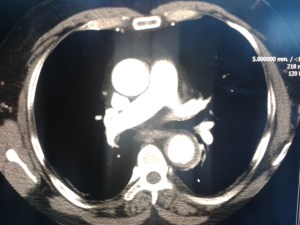

aorta3